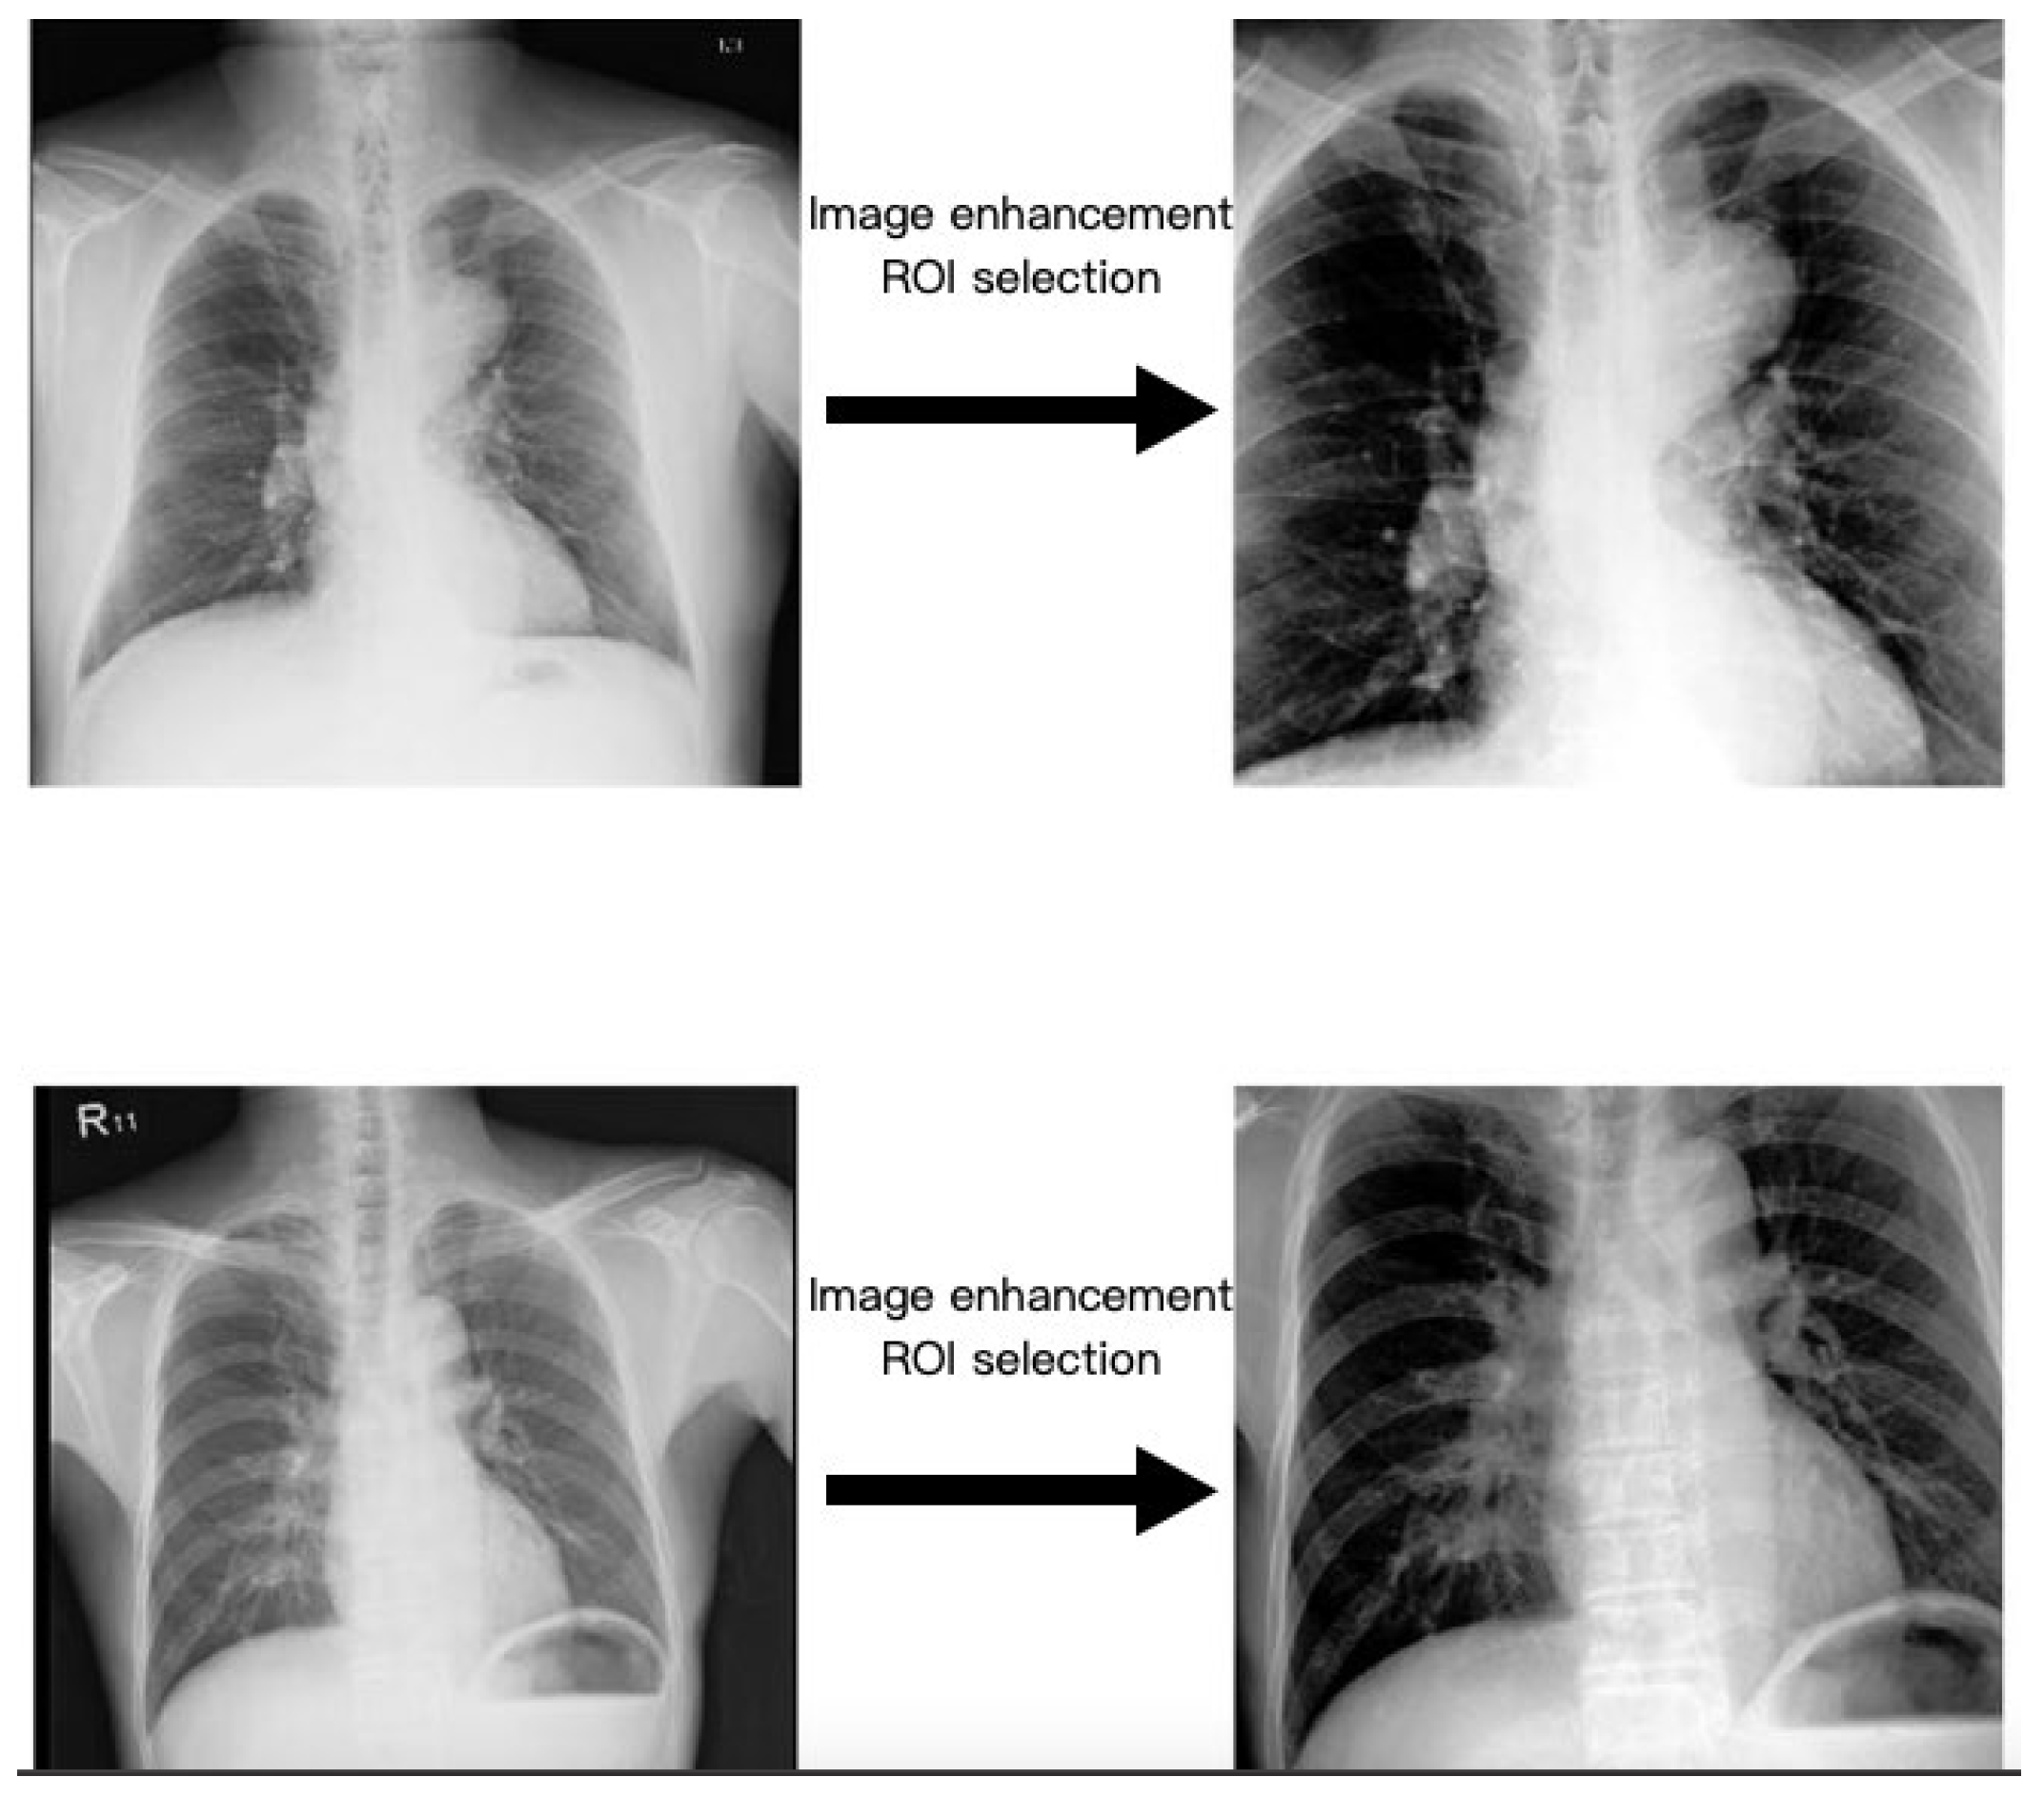

2.3. Region of Interest

2.4. Image Enhancement